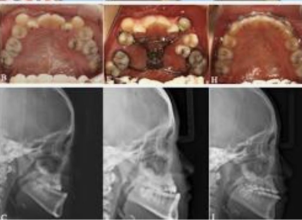

Maxillary prognathism is a dental and facial condition in which the upper jaw extends forward more than normal in relation to the lower jaw. This condition can affect the overall balance of the face and may lead to difficulties with proper bite alignment, chewing, and speech. In many cases, maxillary prognathism develops due to genetic factors, abnormal jaw growth, or developmental conditions that affect the structure of the facial bones.

Patients with maxillary prognathism often experience an excessive overlap of the upper teeth over the lower teeth, commonly referred to as an overbite. This misalignment can sometimes lead to discomfort in the jaw, uneven wear of teeth, and difficulties in maintaining proper oral hygiene. Early diagnosis is important in order to determine the most suitable treatment approach and prevent further complications. Treatment for maxillary prognathism depends on the severity of the condition and the age of the patient. In mild cases, orthodontic treatments such as braces or aligners may help correct the alignment of the teeth. However, in more severe cases where the jaw structure is significantly affected, orthognathic surgery may be recommended. This surgical procedure repositions the upper jaw to achieve better facial balance and proper bite alignment. Modern dental and surgical techniques allow specialists to carefully plan and perform these procedures with high precision. With proper treatment and follow-up care, patients can achieve improved jaw function, better facial harmony, and a more confident smile. Maxillary prognathism treatment plays an important role in restoring both functional and aesthetic aspects of oral health.